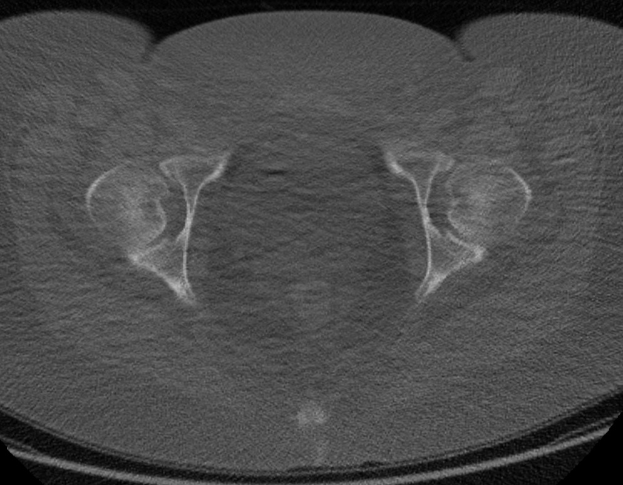

Krebs kann auch in anderen Bereichen der Harnwege auftreten, etwa in der Blase, den Nieren oder den Hoden. Die Früherkennung durch PSA-Tests bleibt dennoch von zentraler Bedeutung, da eine späte Diagnose die Behandlungsmöglichkeiten einschränkt.